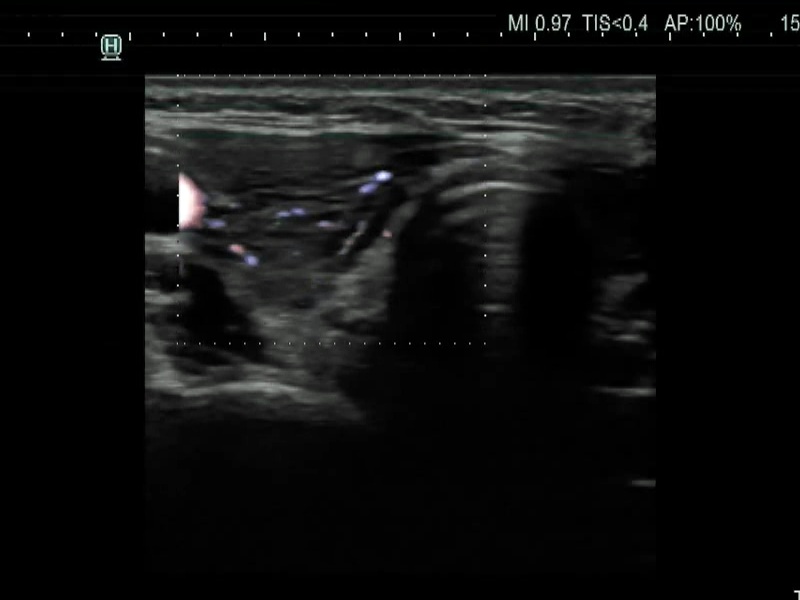

Ultrasonography. The thyroid was moderately hypoechoic and presented with numerous more and less hypoechoic discrete lesions. The largest of the latter was in the lower ventromedial part of the left lobe and had cystic areas and intranodular echogenic figures. The latter included typical comet tail artifacts, back wall cystic figures and some ambiguous small bright granules. The lesion showed both perinodular and intranodular vascularity. Compared with the former examination the nodule increased by 22% in volume. This difference is within the intraobserver variation.